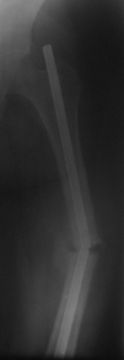

Refractura femorae

Уважаемые коллеги. Обратилась б-ная Д, 32 г с рефрактурой с/з диафиза левой бедренной кости со сломанным штифтом и с 20-ти дневным новорожденным ребенком на руках.

Со слов 10.11.05 г. оперирована в БСМП , видимо произведена ОИМО штифтом ЦИТО, в то время тоже была беременной, перелом якобы долго не срастался, потом ходила с палочкой, после выкидыша повторно забеременела, поправилась на 14 кг и где-то в середине августа заметила отечность и постепенное искривление бедра, к травматологам не обратилась т.к. её цель была сначала родить ребенка. При осмотре отмечается умеренная отечность, рекурвация и варусное искривление на уровне с/з диафиза бедра, патологической подвижности явно не определяется (ну тугая), умеренная болезненность при пальпации, движения в коленном суставе почти в полном объеме . Дорогие участники форума, коллеги ! Помогите советом! 1. Как удалить дистальный обломок штифта? Я знаком с материалом В. Д. Машталова, от 19.10.07г. и рекомендациями А. Н. Челнокова и A. Semenisty, но практически как это делается без рисунков или чертежей не понял, можно ли без ЭОПа делать?. 2. На операц. столе одномоментное закрытое устранение деформации, рассверление к/м канала, и ЗИМО более толстым стержнем(не блокируемым)?? Надо учесть, что бедро короткое и толстое, АВФ сложно да и больная не хочет. НВ-62г/л, эритроц- 2,3млн + новорожденный ребенок. Р-снимок пока только один, б-ная отправлена гематологам. С уважением Абдурашид